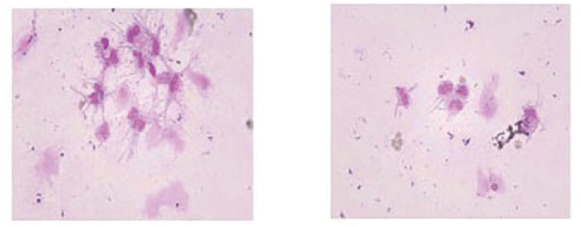

肺癌仍然是世界上最常见的恶性肿瘤之一。随着发病率的增加和医疗技术的发展,肺癌患者的总体生存期较以往有了明显延长。肺癌脑、脑膜转移的发病率也逐年上升,但肺癌脑、脑膜转移患者预后差,死亡率非常高,诊断主要依靠计算机断层扫描(CT)、磁共振成像(MRI)等影像学检查。但其影像学特征多样,特异性低,易误诊漏诊。因此,准确识别脑及脑膜转移灶并及时进行靶向治疗对改善患者预后至关重要。本文分析1例肺癌根治性手术后近7年长期随访无明显复发转移,但近5个月患者行为异常、意识受损、癫痫,头部CT及MRI发现脑内多发点状钙化的诊断与治疗。本文认为患者的精神和行为症状是在排除感染性疾病和自身免疫性脑炎治疗无效后,由肺癌脑、脑膜转移引起的,进一步病理活检和基因检测证实为表皮生长因子受体(EGFR) L858R基因突变的转移性肺腺癌,经奥西替尼靶向治疗后,患者症状得到明显改善。本文还在中国知网、万方、UpToDate、PubMed等数据库中检索了脑钙化的相关文献,发现脑钙化存在于多种疾病中,包括感染性疾病、遗传性和神经退行性疾病、血管疾病、代谢疾病和肿瘤。然而,脑钙化和脑膜转移往往被低估,随之而来的风险是误诊和延误治疗。因此,在既往有肿瘤病史的患者中,表现为脑钙化的脑和脑膜转移不应被忽视。

Lung cancer is still one of the most common malignant tumors in the world. With the increase of its incidence and the development of medical technology, the overall survival of lung cancer patients has significantly extended compared to before. The incidence of brain and meningeal metastases from lung cancer has also been rising year by year, but patients with brain and meningeal metastases from lung cancer have a poor prognosis and a very high mortality rate, and the diagnosis is mainly based on computed tomography (CT), magnetic resonance imaging (MRI) and other imaging examinations. However, the imaging features are diverse and the specificity is low, which makes it easy to be misdiagnosed and missed. Therefore, accurately identifying brain and meningeal metastases and timely targeted treatment is crucial for improving patient prognosis. This paper analyzed the diagnosis and treatment of a case of lung cancer with no obvious recurrence and metastasis in nearly 7-year long-term follow-up after radical lung cancer surgery, but the patient with abnormal behavior, impaired consciousness and epilepsy in the past 5 months, and multiple punctate calcifications in the brain found by head CT and MRI. This paper consider that the patient's mental and behavioral symptoms were caused by brain and meningeal metastasis of lung cancer after excluding infectious disease and ineffective treatment of autoimmune encephalitis, and further pathological biopsy and genetic detection confirmed the diagnosis of metastatic lung adenocarcinoma with epidermal growth factor receptor (EGFR) L858R gene mutation, and the patient's symptoms were significantly improved after targeted therapy by Osimertinib. This paper also searched the relevant literatures of brain calcifications in databases such as China National Knowledge Infrastructure (CNKI), Wanfang, UpToDate, PubMed, etc., and found that intracerebral calcifications exist in a variety of diseases, including infectious, genetic and neurodegenerative diseases, vascular diseases, metabolic diseases and tumors. However, brain calcification in brain and meningeal metastases are often underestimated, and the consequent risk is misdiagnosis and delayed treatment. Therefore, brain and meningeal metastases manifested as brain calcification should not be ignored in patients with a history of previous tumors.